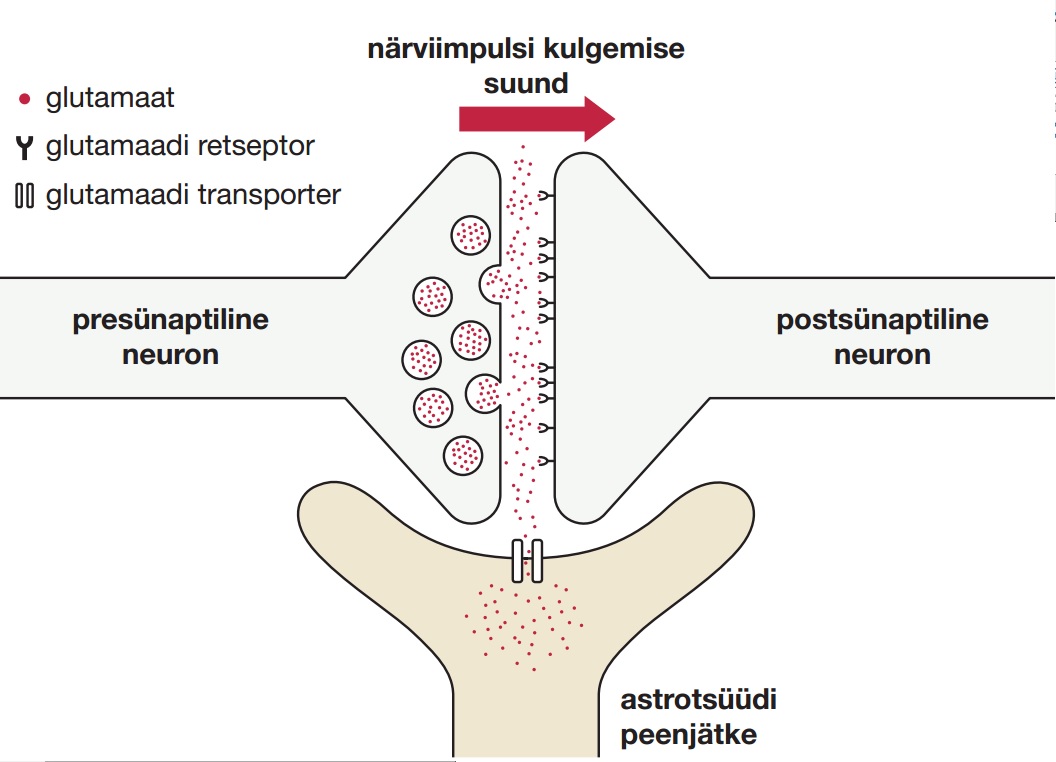

Vaatleme lähemalt mõnda tähtsamat astrotsüütide ülesannet. Esmalt käsitleme sünaptilist homöostaasi. Nagu neuronitel on ka astrotsüütidel palju peenikesi jätkeid. Raku keskpaigast ehk rakukehast lähtuvad jämedamat sorti jätked, mis harunevad järjest peenemaks. Harud lõpevad ülipeenikeste lõppjätketega, mis moodustavad sünapsi ümbritseva ehk perisünaptilise kapsli. Selle nn perisünaptilise jätke ülesanne on osaleda protsessis, mis taastab sünaptilise ülekande järel sünapsis paiknevate ioonide ja virgatsainete algkontsentratsioonid. Allpool oleval joonisel on see protsess esitatud aju kõige levinuma sünapsitüübi ehk glutamaatergilise sünapsi (kasutab virgatsainena aminohapet glutamaat) näitel. Niisugune sünaptiline majapidamistöö peab käima lakkamatult ja kui selles tuleb ette häireid, on tagajärjed halvad. Näiteks võimetus haarata astrotsüüdi lõppjätketesse piisavalt glutamaati toob kaasa glutamaatergiliste sünapside üleergastamise, mis võib ajendada epilepsia tekke. Päriliku epilepsia põhjustajana on teada mitu mutatsiooni astrotsüüdis toimetava glutamaadi transporteri geenis.

Kahest neuronist ja astrotsüüdist koosnev kolmeosaline sünaps: neuronite kokkupuutepunkt, kus närviimpulss kandub ühelt neuronilt teisele. Närviimpulss muundatakse elektrilisest keemiliseks virgatsainete kaudu. Joonisel on virgatsainena kujutatud glutamaati kui neist levinuimat. Glutamaat on koondunud presünaptilisel poolel põiekestesse, mis vabastavad impulsi käigus oma sisu sünaptilisse pilusse. Glutamaat seostub asjaomase retseptormolekuliga, mille tõttu muundatakse sünaptiline vastus uuesti elektriliseks. Viimastel aastakümnetel on välja kujunenud ettekujutus sünapsist kui kolme rakulise poolega struktuurist: peale kahe neuroni osalevad selles astrotsüüdid, mille jätked ümbritsevad sünapsi. Joonisel olevat astrotsüüdijätket tuleb kolmemõõtmelises ruumis ette kujutada nõnda, et ta ümbritseb neuronitevahelist kontakti. Üks astrotsüütide oluline roll sünaptilises ülekandes on eemaldada liigne glutamaat rakkudevahelisest ruumist. Niisugune mehhanism tagab selle, et sünaps on valmis vastu võtma uut impulssi ehk informatsiooni